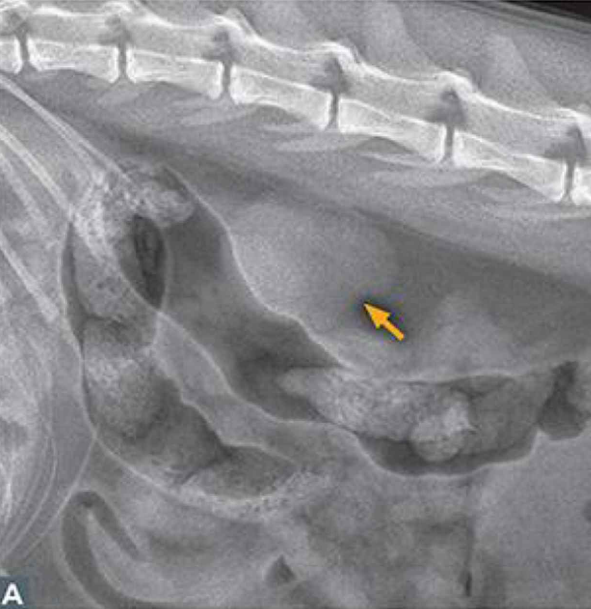

Imaging

- ์นผ์์ด ๊ณผ๋ํ๊ฒ ๋น ์ ธ๋๊ฐ๋ ์ด์์ด

- ์ ์ฒด์ ์ผ๋ก ๋ผ ๋ฐ๋ ๊ฐ์ ์์

- ์๊ตฌ ์กฐ์ง mineralization

- ์ด์ํ๋ง์ผ๋ก๋ 1/2๊ธฐ ๊ตฌ๋ถ ์ด๋ ค์